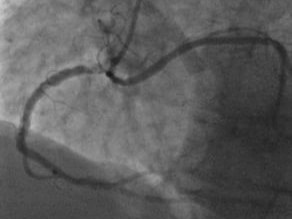

Do you think Dr. Sameh Sayfo, MD, MBA, FSCAI, FACC has what it takes to earn the title of TopShock? Join us at our TCT Conference symposium on October 25 to see how Dr. Sayfo successfully treated a complex calcified nodule in the prox RCA. blog.shockwavemedical.com/topshock2023fi… US Rx only. ISI bit.ly/3iEq7fC